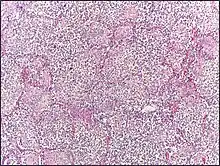

- Red hepatization or consolidation: Vascular congestion persists, with extravasation of red blood cells into alveolar spaces, along with increased numbers of neutrophils and fibrin. The filling of airspaces by the exudate leads to a gross appearance of solidification, or consolidation, of the alveolar parenchyma. This appearance has been likened to that of the liver, hence the term "hepatization".

- Grey hepatization: Red blood cells disintegrate, with persistence of the neutrophils and fibrin. The alveoli still appear consolidated, but grossly the color is paler and the cut surface is drier. This is when death typically occurs in severe cases.